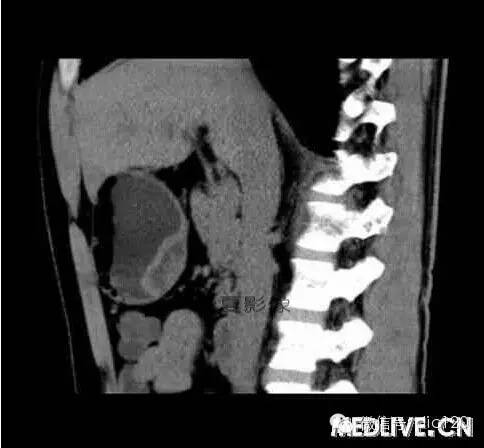

男,36歲,間斷性返酸噯氣3年,3個月前出現(xiàn)上腹疼痛,饑餓時加重。圖1-3為CT平掃,圖4-6分別為CT增強(qiáng)掃描的動脈期、門脈期和延遲期。

CT檢查可見胃幽門前區(qū)胃小彎側(cè)胃壁局限性增厚、隆起或伴凸向胃腔內(nèi)的小結(jié)節(jié)灶,寬基地,境界光整,注射對比劑,增強(qiáng)掃描后,CT值可達(dá)50HU以上,與正常胰腺強(qiáng)化相仿。

胃迷走胰腺大多位在距幽門1-6cm的胃竇胃大彎側(cè),粘膜下層內(nèi),為1-3cm大小的病灶。 與胃壁以寬基底相,增強(qiáng)掃描病灶表面覆蓋的黏膜明顯強(qiáng)化且連續(xù),病灶內(nèi)無明顯壞死,病變強(qiáng)化方式類似于正常胰腺組織;當(dāng)病灶出現(xiàn)邊緣臍凹征或中央導(dǎo)管征時,對EP的診斷具有一定的特異性。